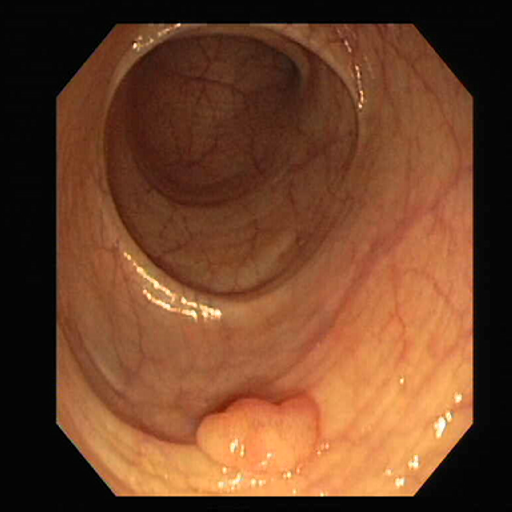

Qualitative Evaluation

Fig. 7 offers qualitative validation, showcasing MNet-SAt’s superior polyp mask generation compared to baselines across four cases. This qualitative superiority aligns with the previously established quantitative results. In the case of small polyps (first and fifth rows), all baseline methods initially appear to produce satisfactory visual results. However, upon closer inspection, they fail to maintain fine boundary details. Our framework excels in preserving polyp anatomy and topology for medium and large polyps, significantly outperforming the baseline methods. Notably, even in multiple polyps, our framework successfully captures more polyps and approximates the ground truth more closely. The primary reason for this superior performance is the EGFE module, which effectively eliminates noise in conjunction with the HMAtt module, resulting in a few false positives. Our analysis reinforces MNet-SAt’s effectiveness in handling challenging polyp scenarios (small, medium, large-scale, and multi-polyps) while suppressing non-regions of interest.

Refer to caption

Fig. 7: Qualitative comparison of MNet-SAt segmentation outputs with existing baselines